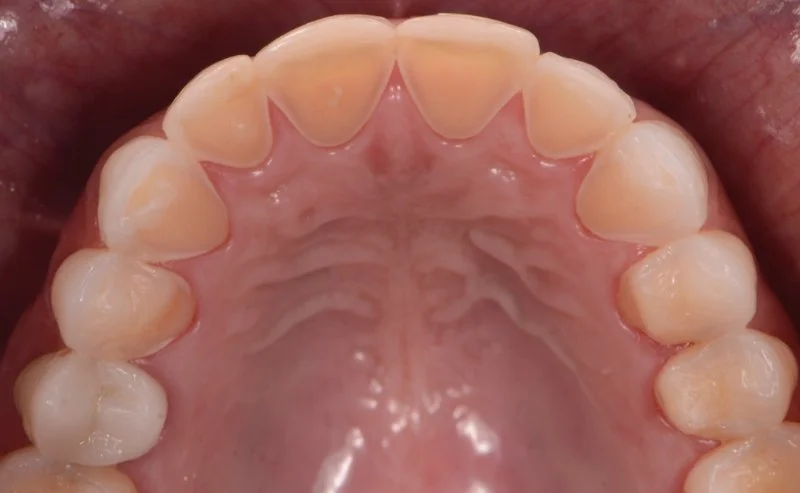

Lack of room for the tongue (narrow palate, tongue-tied, lingually tipped teeth)

In adults with narrow palate, we expand the palate and the nasal airway using miniscrew-assisted rapid palatal expander (MARPE), distraction osteogenesis for maxillary expansion (DOME), or surgery-assisted rapid palatal expander (SARPE). We are one of the three major MARPE providers in the Southern California. For MARPE, we perform Piezo corticotomy on the palatal suture in our office, under local anesthesia, to aid the opening of the palatal suture in adults. You can go about your day immediately after the MARPE installation. MARPE is always followed by a full orthodontic treatment, and the temporary gap that develops between the top front teeth will be closed quickly. With 10+ years of experience and having done more than 300 MARPE cases at 98% success rate, Dr. Long will make the MARPE journey as smooth and comfortable as possible.